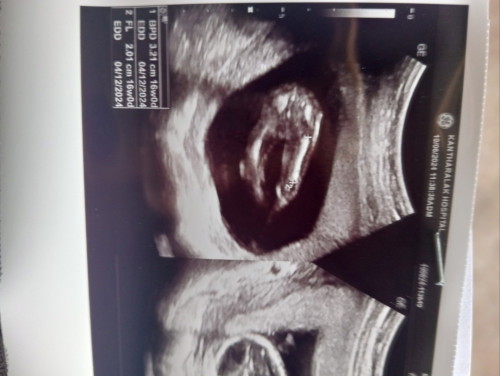

ช่วยดูหน่อยค่ะว่าผู้หญิงหรือผู้ชาย

น้องผู้หญิงหรือผู้ชายค่ะ

90% คือผู้หญิงนะคะคุณแม่เพราะน้องหนีบ

กำลังตั้งครรภ์